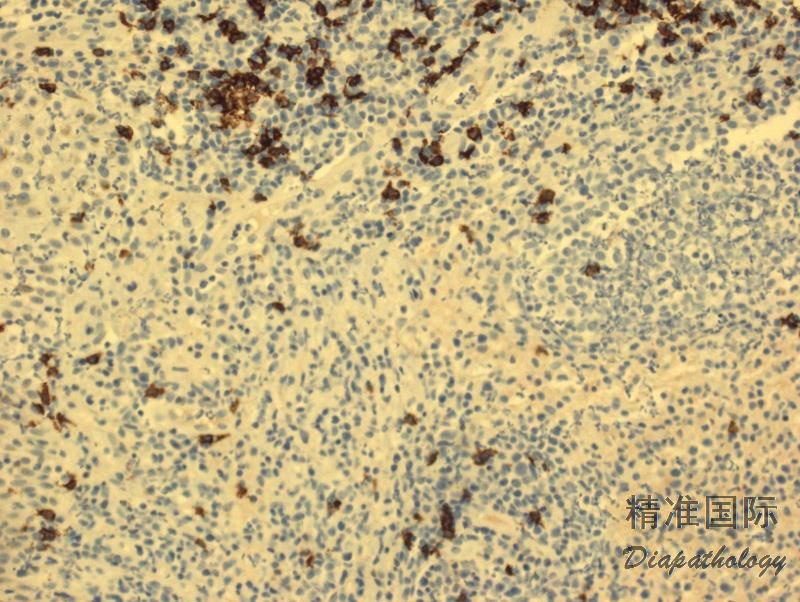

免疫表型:大异形肿瘤细胞(A,C 型)表达 CD30 和细胞毒分子,常表达 CD4,但其它 T 细胞相关抗原常阴性。 B 型肿瘤细胞表达 CD3 和 CD4,但不表达 CD30 和 CD8。 D 和 E 型肿瘤细胞表达 CD30. CD3. CD8,不表达 CD4。DUSP22-IRF4 病例表达 CD8 或 CD4/CD8 双阴性,CD30 弱或强阳性。所有亚型都不表达 ALK,EMA 一般也阴性,有个 1 别报道表达 CD56。